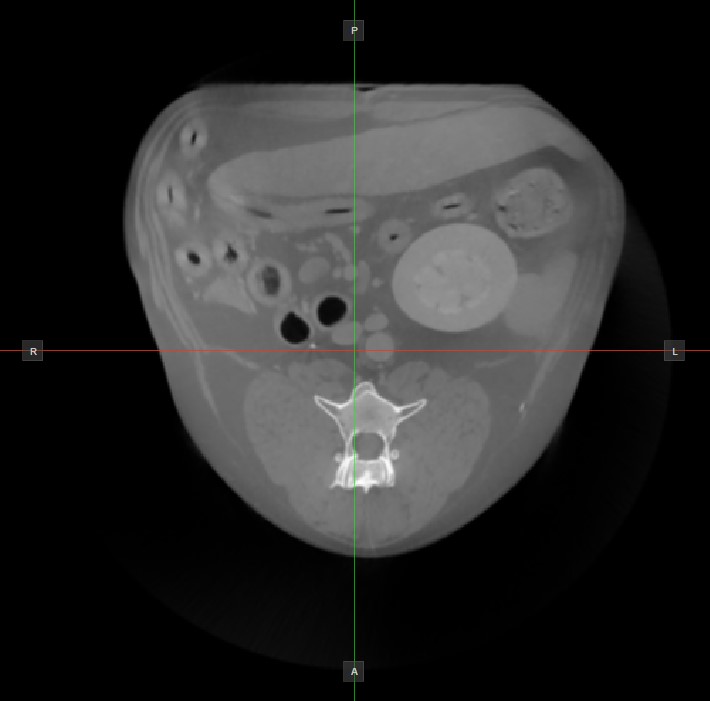

Image Orientation and Image Planes¶

The position and intersection of the other two image planes not represented in the active viewport is indicated by two vertical and horizontal lines called slicers. The endpoints of each slicer are labeled with a letter that corresponds to the appropriate direction/side of the 3D volume, based on the RAS coordinate system.

Only four sides of the available six are indicated on each 2D viewport. The labels and the corresponding side are the following:

Patient Right (R), indicating the right side of the body

Patient Left (L), indicating the left side of the body

Anterior (A), indicating the front side of the body

Posterior (P), indicating the back side of the body

Superior (S), indicating the top side of the body

Inferior (I), indicating the bottom side of the body